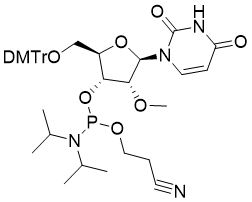

馬鞍山致研生物醫(yī)藥科技有限公司成立于馬鞍山市鄭浦港新區(qū)現(xiàn)代產(chǎn)業(yè)園。公司專(zhuān)注于生物小分子、醫(yī)藥中間體相關(guān)產(chǎn)品的研發(fā)和生產(chǎn),產(chǎn)品主要包括DNA亞磷酰胺單體、RNA亞磷酰胺單體、特殊單體以及按照客戶(hù)要求定制的RNA和DNA,并且公司提供定制合成等方面的研究服...

馬鞍山致研生物醫(yī)藥科技有限公司成立于馬鞍山市鄭浦港新區(qū)現(xiàn)代產(chǎn)業(yè)園。公司專(zhuān)注于生物小分子、醫(yī)藥中間體相關(guān)產(chǎn)品的研發(fā)和生產(chǎn),產(chǎn)品主要包括DNA亞磷酰胺單體、RNA亞磷酰胺單體、特殊單體以及按照客戶(hù)要求定制的RNA和DNA,并且公司提供定制合成等方面的研究服...